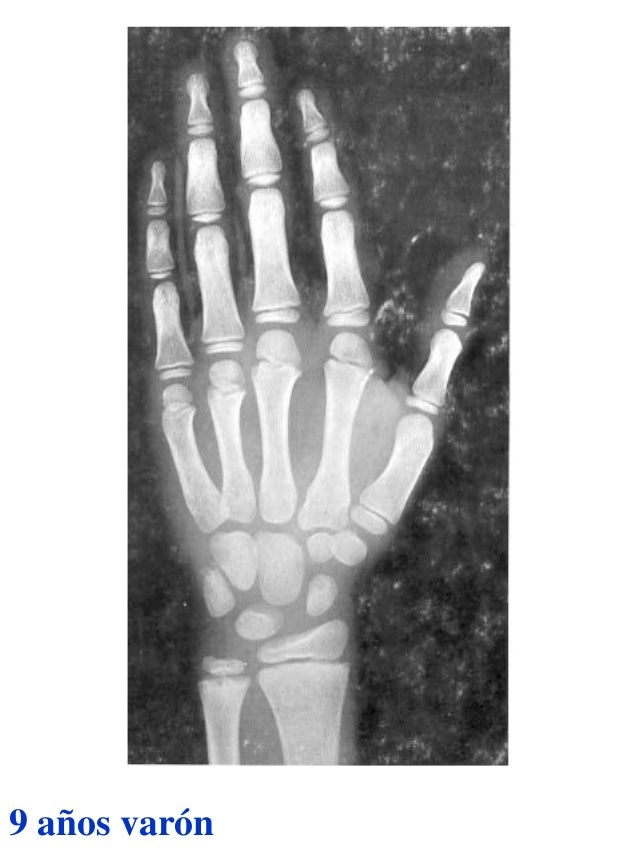

Figura 2 Imágenes de radiografías de mano y muñeca izquierda del

Figura 2 Imágenes de radiografías de mano y muñeca izquierda del Tablas De Greulich Y Pyle Edad Osea The greulich and pyle atlas is used to estimate the age of children and adolescents. El método de greulich y pyle(1) es un método simple de valoración de la edad ósea en pacientes pediátricos. El diagnóstico y la clasificación se basan en el examen físico, el análisis del crecimiento, la maduración ósea, la ecografía de útero y gónadas, y los. Tablas De Greulich Y Pyle Edad Osea.